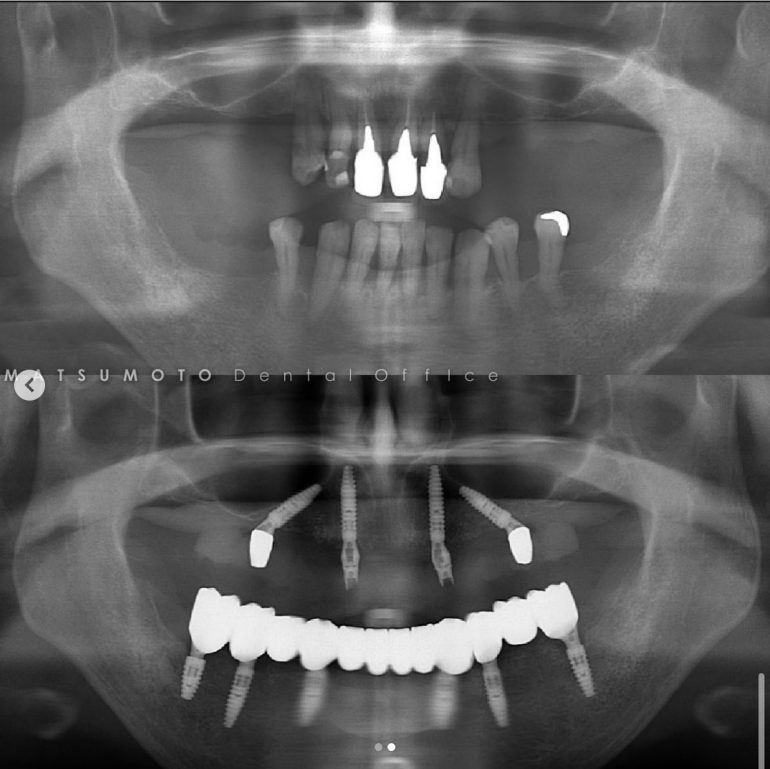

パノラマX線

上顎:根の病気と虫歯で保存不可のな状態。

下顎:インプラントが不適切な位置に入っており、撤去が必要な状態。

オールオンシックス(All-on-6)インプラント治療を終えて

最終補綴

上顎:両側サイナスリフト後のロケーターアバットメントによる金属床ブリッジ

下顎:All-on-6によるフルジルコニアブリッジ

治療のリスクと副作用

治療期間:約1年半

治療費:¥6,200,000(税込)

リスク:上顎のロケーターアバットは定期的に交換が必要です。また、上顎の人工歯が減ってきますので、定期的なメンテナンスが重要です。